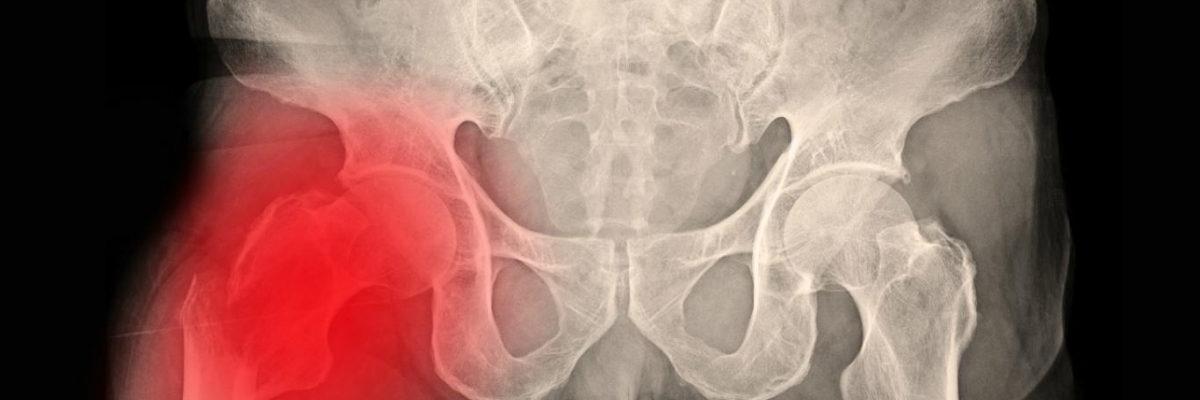

Las fracturas de cadera son una de las lesiones más frecuentes y graves en personas mayores. Tras la cirugía, es fundamental iniciar cuanto antes un proceso de rehabilitación fisioterapéutica, que no siempre requiere desplazamientos a una clínica. Gracias a la fisioterapia a domicilio, es posible recuperar la movilidad, mejorar la fuerza y prevenir complicaciones sin salir del entorno habitual. En FisioClinics La Moraleja, ofrecemos programas adaptados de fisioterapia en casa para la recuperación funcional tras una fractura de cadera.

Después de una fractura y posterior intervención quirúrgica (como una artroplastia o fijación con clavos), muchos pacientes presentan: